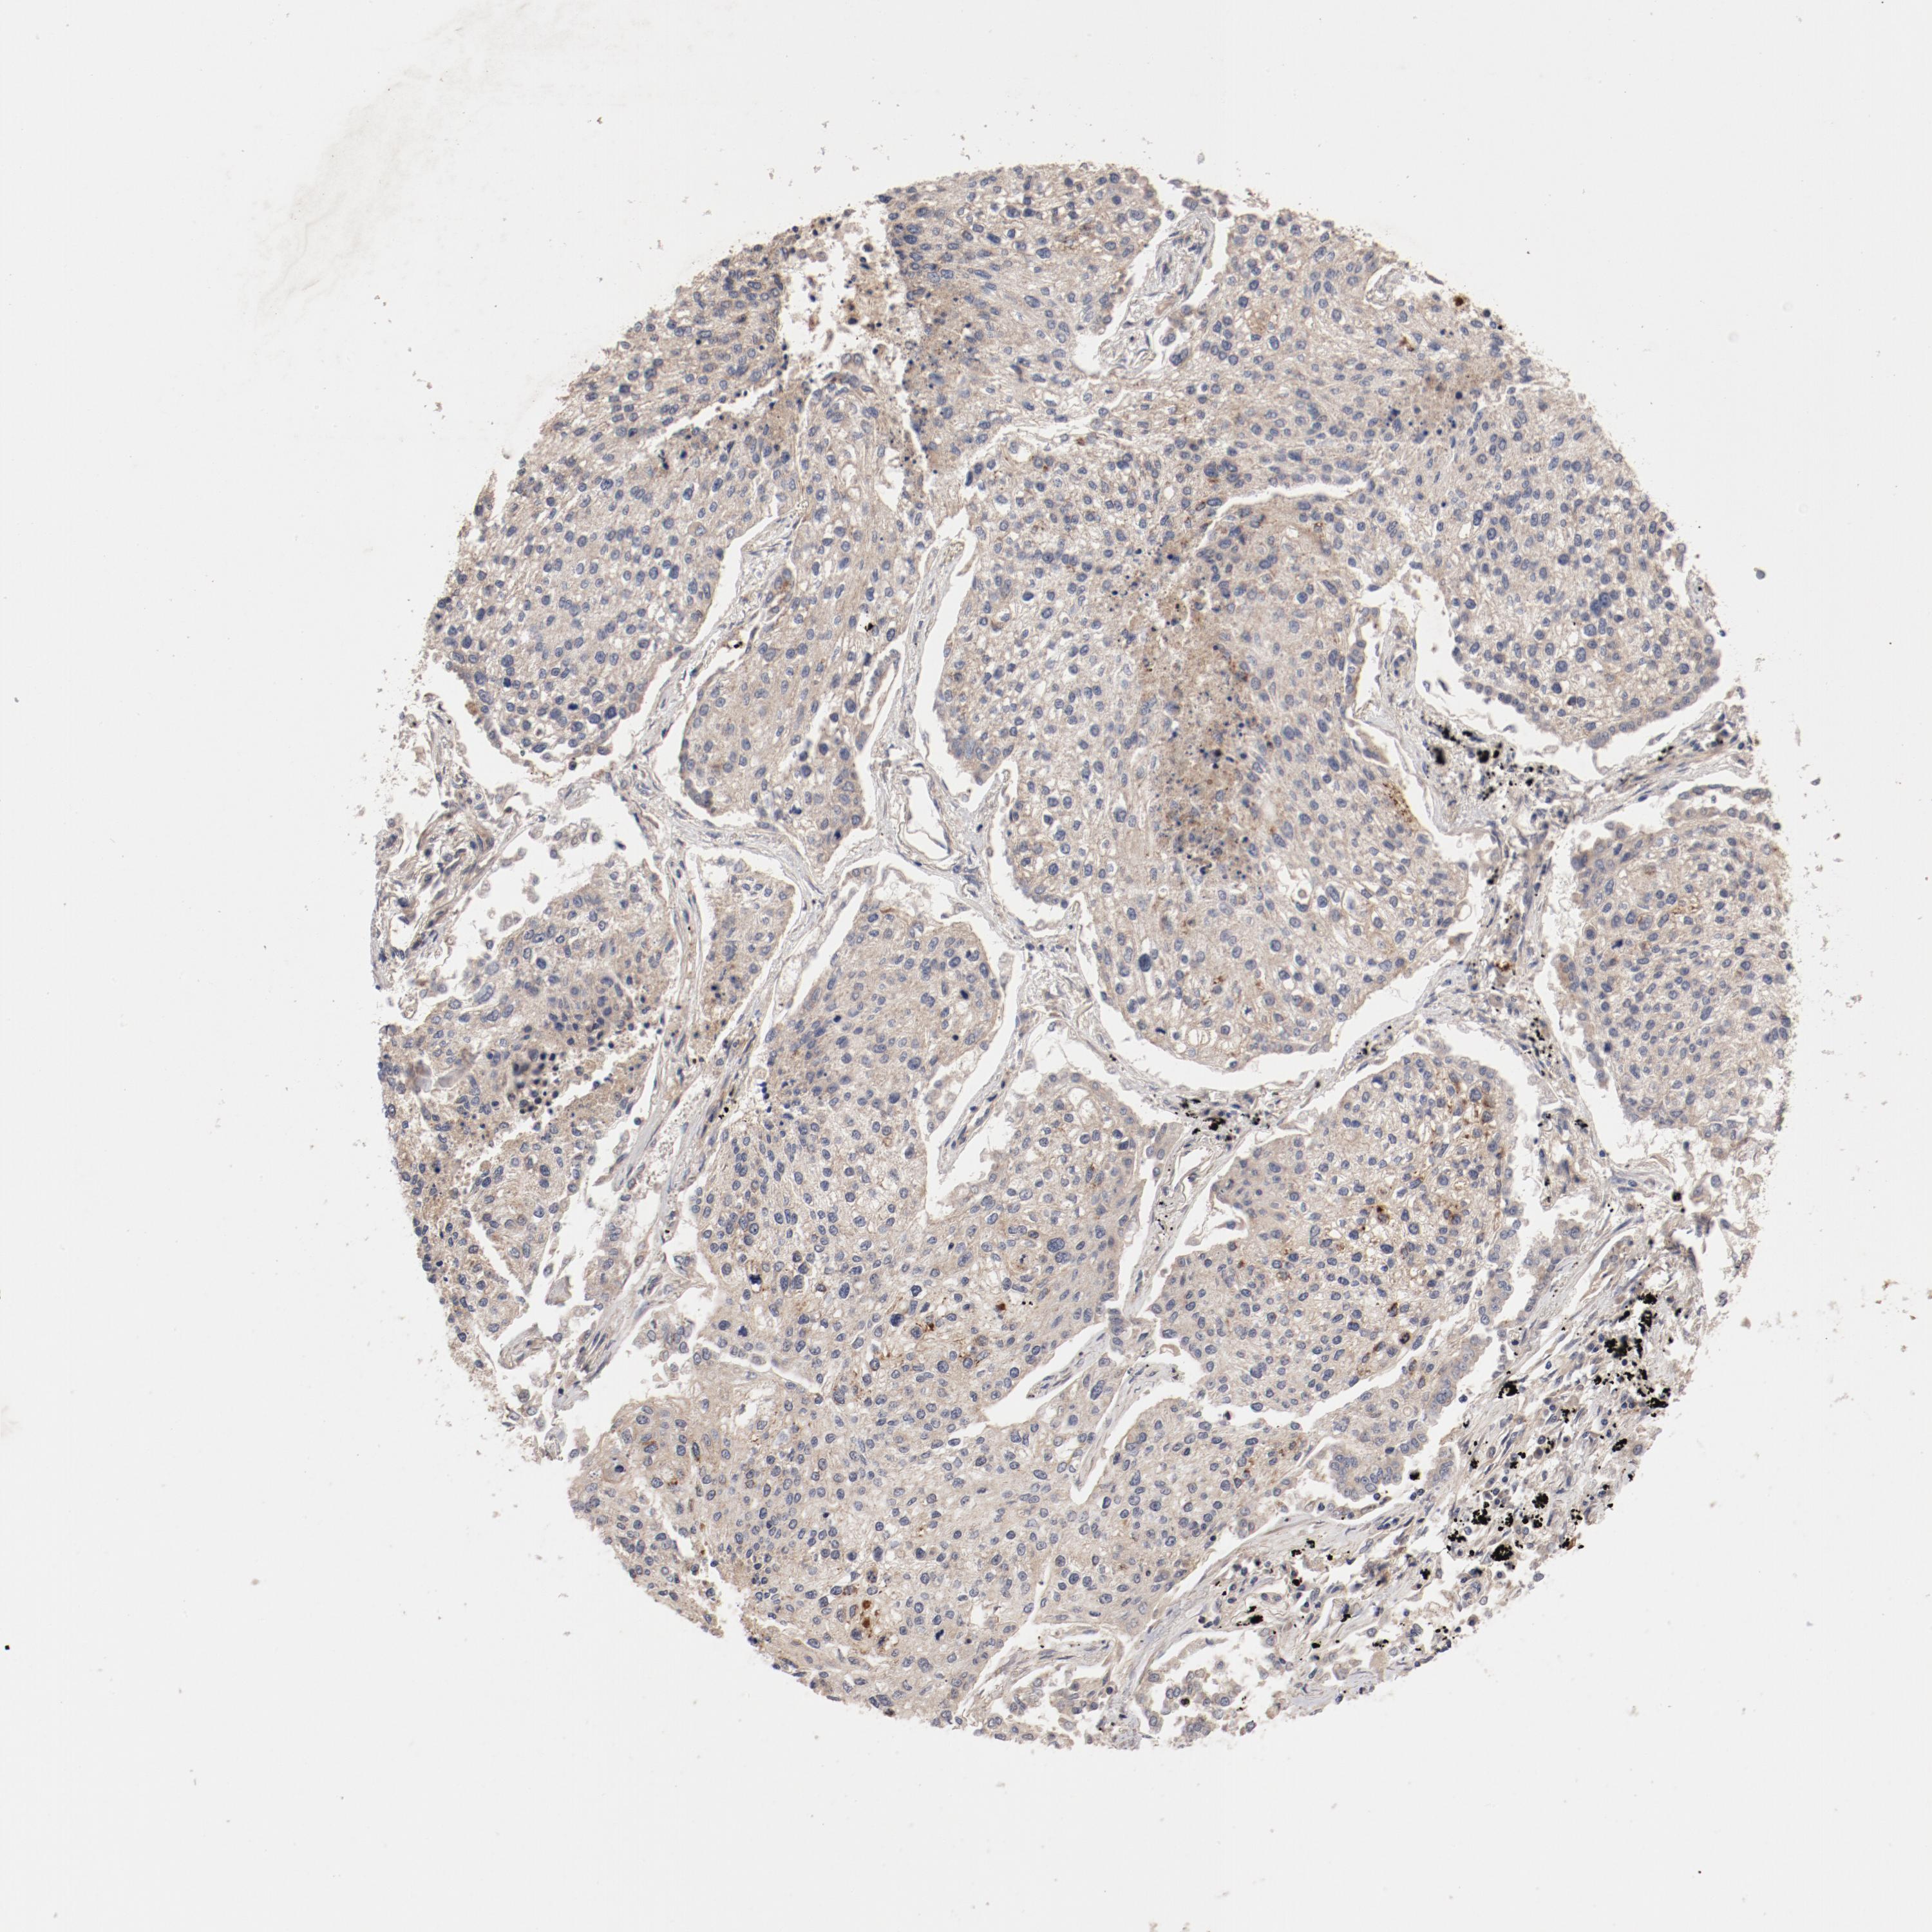

LUNG ADENOCARCINOMA (TCGA) - Interactive survival scatter ploti

The Survival Scatter plot shows the clinical status (i.e. dead or alive) for all individuals in the patient cohort, based on the same data that underlies the corresponding Kaplan-Meier plots. Patients that are alive at last time for follow-up are shown in blue and patients who have died during the study are shown in red.

The x-axis shows the expression levels (FPKM) of the investigated gene in the tumor tissue at the time of diagnosis. The y-axis shows the follow-up time after diagnosis (years). Both axes are complimented with kernel density curves demonstrating the data density over the axes. The top density plot shows the expression levels (FPKM) distribution among dead (red) and alive patients (blue). The right density plot shows the data density of the survived years of dead patients with high and low expression levels respectively, stratified using the cutoff indicated by the vertical dashed line through the Survival Scatter plot. This cutoff is automatically defined based on the FPKM cutoff that minimizes the p-score. The cutoff can be changed by dragging the vertical line or by entering a cutoff value in the square labeled "Current cut-off".

Under the Survival Scatter plot the p-score landscape (black curve; left axis) is shown together with dead median separation (red curve; right axis). Dead median separation is the difference in median mRNA expression between patients who have died with high and low expression, respectively. It is calculated as follows: median FPKM expression of dead patients with high expression - median FPKM expression of dead patients with low expression. This is intended to aid the user in visually exploring custom cutoffs and the associated p-scores and dead median separation.

Individual patient data is displayed and can be filtered by clicking on one or more of the category buttons on the top of the page. Categories describing expression level and patient information include: high, low, alive, dead, female, male and tumor stages. The scale of the x-axis can be toggled between linear and log-scale by clicking on the "x log" button. Mouse-over function shows TCGA ID, patient information and mRNA expression (FPKM) for each patient.

& Survival analysisi

Kaplan-Meier plots summarize results from analysis of correlation between mRNA expression level and patient survival. Patients were divided based on level of expression into one of the two groups "low" (under cut off) or "high" (over cut off). X-axis shows time for survival (years) and y-axis shows the probability of survival, where 1.0 corresponds to 100 percent.

GUF1 is not prognostic in Lung Adenocarcinoma (TCGA)

: 4.41